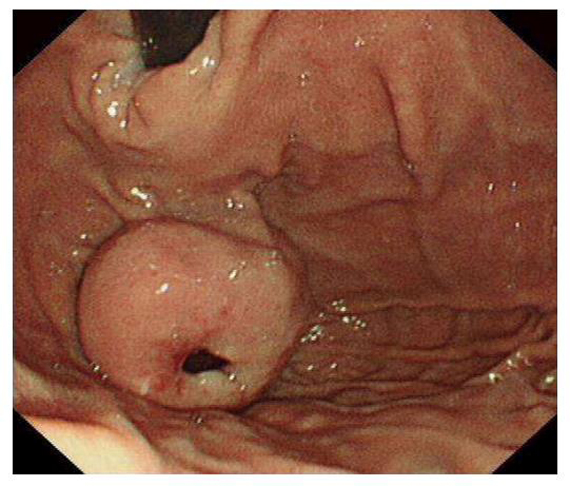

Τις περισσότερες φορές η διαπίστωση ενός στρωματικού όγκου είναι τυχαίο γεγονός, κατά την διενέργεια γαστροσκόπησης ή κολονοσκόπησης ή αξονική τομογραφία κοιλίας.

Μπορεί να αναπτύσσονται ένδο αυλικά, δηλαδή να προβάλουν εντός του οργάνου, όπως για παράδειγμα να προβάλουν εντός του στομάχου υποβλεννογόνια. Ενώ σε άλλες περιπτώσεις, εξελίσσονται έξω αυλικά, δηλαδή εξωτερικά του τοιχώματος του οργάνου. Οι ενδο αυλικά αναπτυσσόμενοι στρωματικοί όγκοι, ανακαλύπτονται σχετικά πρώιμα λόγω συμπτωμάτων απόφραξης ή αιμορραγίας, ενώ αντίθετα οι έξω αυλικά αναπτυσσόμενοι στρωματικοί όγκοι, κατά κανόνα, διαγιγνώσκονται καθυστερημένα και μπορεί να αναγνωριστούν όταν προκαλέσουν επιπλοκές.

Όταν υπάρχει υποψία στρωματικού όγκου, είτε ως τυχαίο εύρημα, είτε στα πλαίσια διερεύνησης συμπτωμάτων ή αιμορραγίας, τότε είναι απόλυτα απαραίτητα η λήψη αντιπροσωπευτικών βιοψιών.

Ανάλογα με την θέση εντοπισμού ενός στρωματικού όγκου, η γαστροσκόπηση ή κολονοσκόπηση είναι απαραίτητες για την προσέγγιση των όγκων του πεπτικού. Με τις εξετάσεις αυτές αξιολογείτε η θέση ανάπτυξης του όγκου, στο τοίχωμα του οργάνου, το μέγεθος τους, και λαμβάνονται υποβλεννογόνιες βιοψίες.